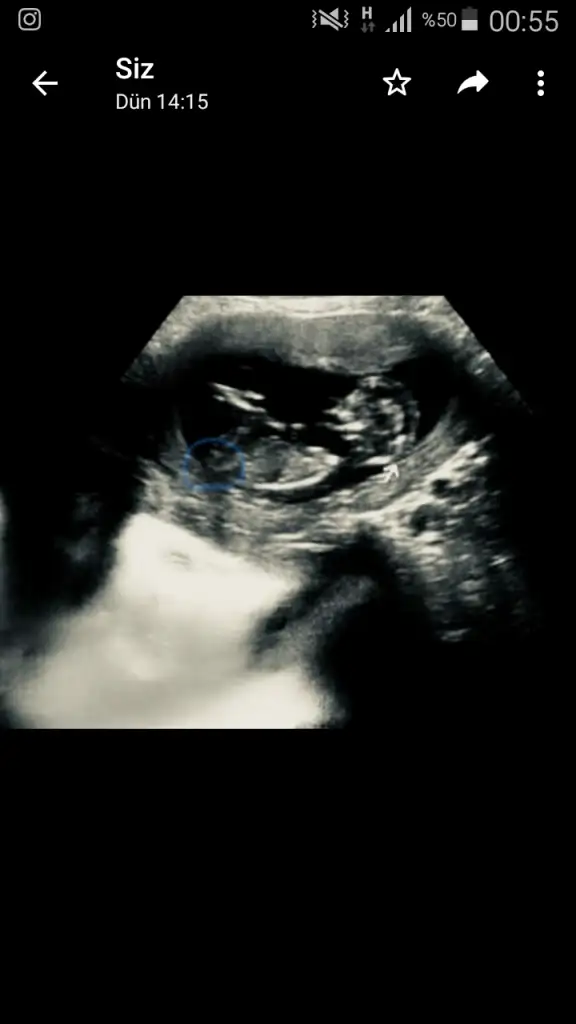

bana da bir tahminde bulunabilir misiniz

Eklentiler

• 15620709920562017048240196490695.webp

45 KB · Görüntüleme: 144